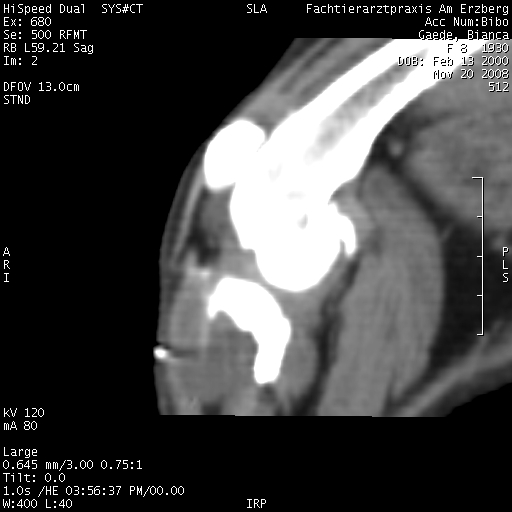

Im CT mit Kontrastmittel hat man den Riss nicht sehen können, nur die Flüssigkeitsansammlung im Knie.Persönlich, wenn es unklar ist, sprich auch der Schubladentest negativ ist, würde ich wohl eher ein MRT machen lassen, wenn die Möglichkeit besteht.

Ich finde, so wirklich erkennen kann man nicht, daß das Kreuzband gerissen ist. Klar, die Arthrose kann man sehen und mehr Flüssigkeit, aber sonst